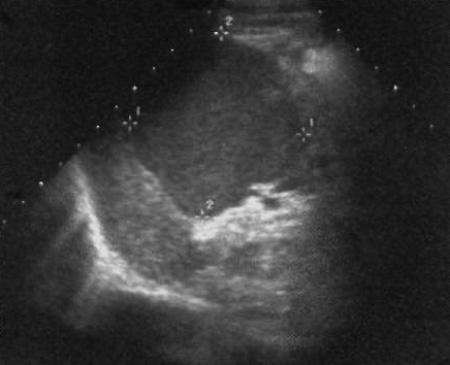

Посттравматическая псевдокиста по сути является гематомой селезенки на последней стадии развития. У таких образований отсутствует эпителиальная выстилка, что и обуславливает их название – псевдокиста (фото 2).

Фото 2. Геморрагическая киста селезенки. Курсорами отмечено поражение с эхогенным детритом и четкими границами – геморрагическая киста селезенки, образованная, вероятно, вследствие травмы

Несмотря на то, что эти образования считаются посттравматическим состоянием, факт травмы в анамнезе присутствует примерно у 25% пациентов (при этом нельзя исключать вариант, что травма могла быть давней и пациент о ней забыл). Во многих случаях посттравматические псевдокисты селезенки содержат периферические кальцинаты (чаще, чем эпителиальные кисты).

Постравматические кисты – наиболее распространенный вариант кистозного поражения селезенки.